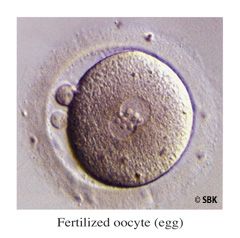

Paso 4: Evaluación de la Fertilización: 14 a 18 horas después de que el espermatozoide y el huevo se colocan juntos, son evaluados por el embriólogo para que confirme la fertilización. Si ocurre la fertilización, los cigotos (o huevos fertilizados) se cultivan para prepararlos para la transferencia (o implantación) del embrión. Durante los próximos días el embriólogo observara continuadamente y determinará la calidad del embrión. La calidad del embrión determinará cuándo se llevará a cabo la transferencia de embriones y la cantidad de embriones que se transferirán. Dependiendo del número de huevos fertilizados, algunos pueden congelarse para su utilización en un proximo ciclo.

Paso 4: Evaluación de la Fertilización: 14 a 18 horas después de que el espermatozoide y el huevo se colocan juntos, son evaluados por el embriólogo para que confirme la fertilización. Si ocurre la fertilización, los cigotos (o huevos fertilizados) se cultivan para prepararlos para la transferencia (o implantación) del embrión. Durante los próximos días el embriólogo observara continuadamente y determinará la calidad del embrión. La calidad del embrión determinará cuándo se llevará a cabo la transferencia de embriones y la cantidad de embriones que se transferirán. Dependiendo del número de huevos fertilizados, algunos pueden congelarse para su utilización en un proximo ciclo.